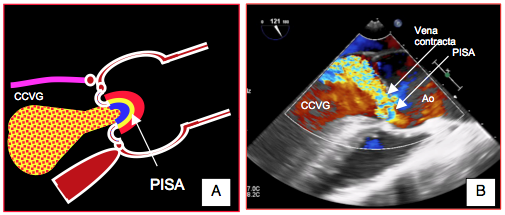

- Recherche et quantification d’une insuffisance aortique (IA) résiduelle, qui peut être paravalvulaire (entre la prothèse et l’anneau aortique) ou intravalvulaire (entre les feuillets de la prothèse) (Tableau 27.9, ci-dessous). La quantification de l'IA comprend l'addition de la fuite intravalvulaire et de la fuite paravalvulaire, c'est-à-dire la charge de volume totale imposée au VG [9]. Le volume régurgité est la différence entre le volume systolique (S • ITV) à travers la CCVG et le volume systolique à travers la CCVD. Les signes d’une IA majeure sont les suivants (vues court-axe 40°, long-axe 120°, transgastrique profonde (0°) et transgastrique long-axe (120°) (Tableau 10.4 ci-dessous):

- Zone d'accélération concentrique (PISA) bien visible sur le versant aortique (voir Figure 26.88).

Figure 26.88 : PISA dans l'insuffisance aortique. A: sa forme hémisphérique n'est visible que dans les IA centrales majeures. B: la zone d'accélération concentrique est très déformée dans les IA excentriques.